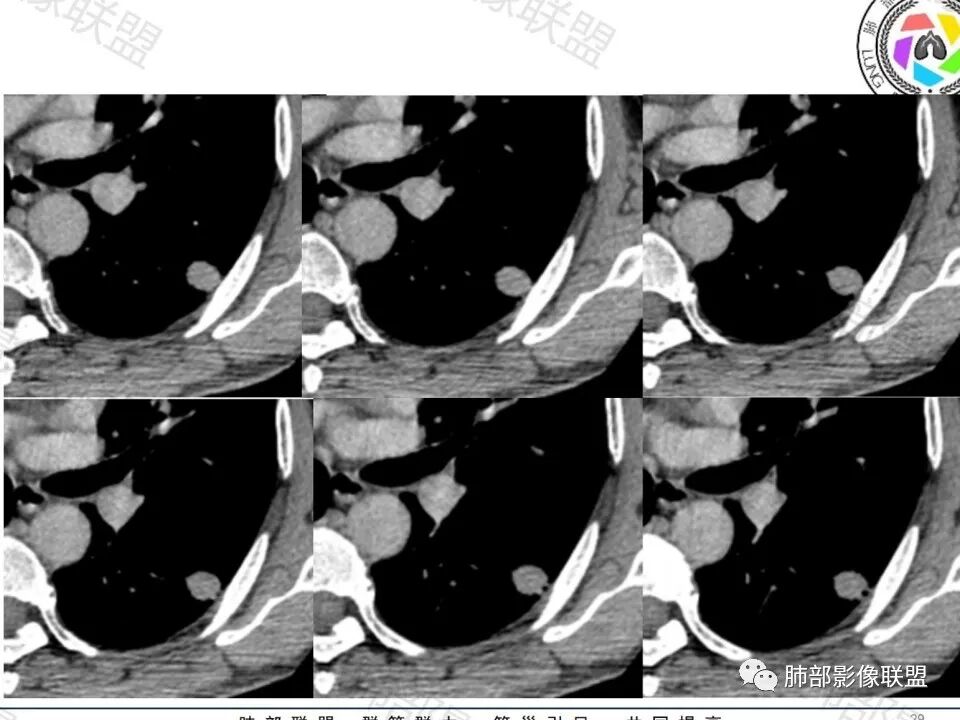

男,60体检发现左肺下叶结节,左肺下叶类圆形结节影,边界清晰,边缘见浅分叶及细短毛刺,病灶内见增粗血管影穿行,相应层面胸膜增厚,双肺另见微小结节影,增强扫描病灶轻度强化,考虑隐球菌,除外腺癌。

老年男性,左肺下叶背段胸膜下孤立结节,整体圆顿,周围有晕,晕中毛刺,似乎支持隐球,但边缘有一囊腔,恶性不能除外!等答案!

支持腺癌,实变为主,周围有晕,血管穿过,考虑粘液腺癌可能性大

左肺下叶胸膜下类圆形结节,无分叶,无胸膜牵拉,周围有晕,血管支气管进入,考虑隐球菌

左肺下叶结节,边缘毛刺,见增粗血管影,临近胸膜增厚,腺癌可能。

左下肺、右中肺均有结节,左下肺病灶比较鼓,边缘有晕,血管弯,持续性强化,考虑腺癌可能,鉴别两处病灶如果一元论,肉芽肿炎 (隐球)

左肺下叶胸膜下实性小结节,边缘可见毛刺,轻度收缩,近端与血管束相连,远端轻度牵拉胸膜,并远端可见小空泡,平扫密度均匀,增强后渐近性强化,考虑腺癌,鉴别隐球菌

老年男性,CT左肺下叶胸膜下类圆形结节,边缘光滑,无分叶,可见毛刺,相邻胸膜多条牵拉,局部胸膜增厚,(多见炎性病变),病灶周围可见模糊晕征,血管支气管进入,考虑隐球菌,现实中万万不能排除肺癌。

中老年男性患者,无症状体检发现,胸部CT:左下肺内前基底段近胸膜下类圆形结节,边缘清晰,周围晕征,周围毛刺细软,有胸膜牵拉及血管进入,增强扫描明显不均匀强化,考虑炎性肉芽肿,隐球菌可能,鉴别腺癌

图做的真漂亮!老年男性,双肺多发结节,最大者位于左肺下叶胸膜下,周围有晕,晕中毛刺,边缘有一囊腔,胸膜牵拉,持续强化,考虑隐球,鉴别腺癌。

老年男性,查体发现,左肺下叶靠近胸膜下结节,边缘膨隆,胸膜牵拉,有细软毛刺,周围有空泡征?中度强化,有血管进入,收缩力不强感觉,我也考虑隐球菌,鉴别肺癌,粘液腺癌?

那根血管穿进去,短毛刺,老年,先癌后隐球菌

左肺下叶背段结节,短毛刺实性血管集束,增强富血供,不管病理最后怎么样,日常写报告考虑恶性腺癌可能大,建议手术或抗炎后无变化也建议手术。

左肺下叶胸膜下类圆形结节,边缘光滑,周围有晕,晕中有毛刺,周围可见小卫星灶,相邻胸膜增厚,血管进入,右肺中叶可见小结节影,考虑炎性肉芽肿,隐球菌。鉴别腺癌。

晨读:左肺下叶胸膜下实性小结节,边缘可见模糊晕及毛刺,轻度收缩,与支气管关系不清,近端与血管束相连,内见小空泡,平扫密度均匀,均匀强化。远近可见多个小结节。考虑炎性肉芽肿,隐球菌病,鉴别结核、腺癌。

老年男性,左肺下叶背段胸膜下结节,边缘毛刺,血管进入,斜裂有牵拉,局部胸膜糊墙,周围有晕,但有一囊腔,首先考虑腺癌,但是右肺中叶及左肺下叶还有其他结节,鉴别隐球菌

类圆形,边缘稍平直,周围晕中细微毛刺,密度均匀,均匀强化,血管走形自然,稍牵拉扭曲,支气管在近端堵塞

这枚结节的纵隔窗在没有调节窗位的情况下,已经很密实了,说明这个结节里面是软组织的成分,这与普通炎性结节(隐球菌等)的密度还是有区别的,很多年前就有人提出,纵隔窗显示越大,恶性可能越大;

结节周围有磨玻璃影,边界似清不清的,但是总体不如炎性晕征那么模糊;

增强的程度很难讲,但是不均匀强化是可以确定的;

有收缩力,但是很轻,按照常理,实性结节因为有占位效应,不太会有收缩力,但是叶间胸膜有凹陷。所以讲,这个结节还是开了放心。